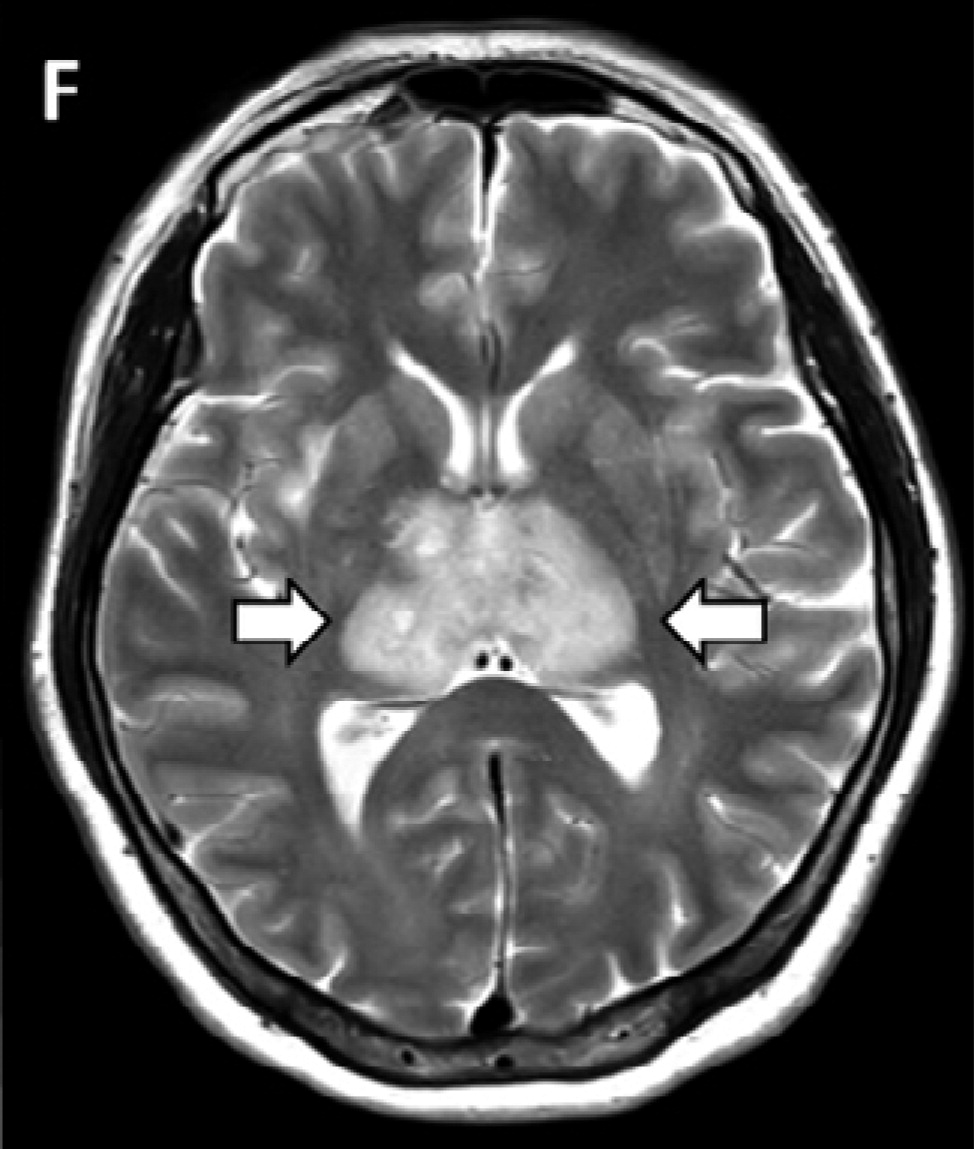

Вернике мрт

Вернике мрт 113 фото